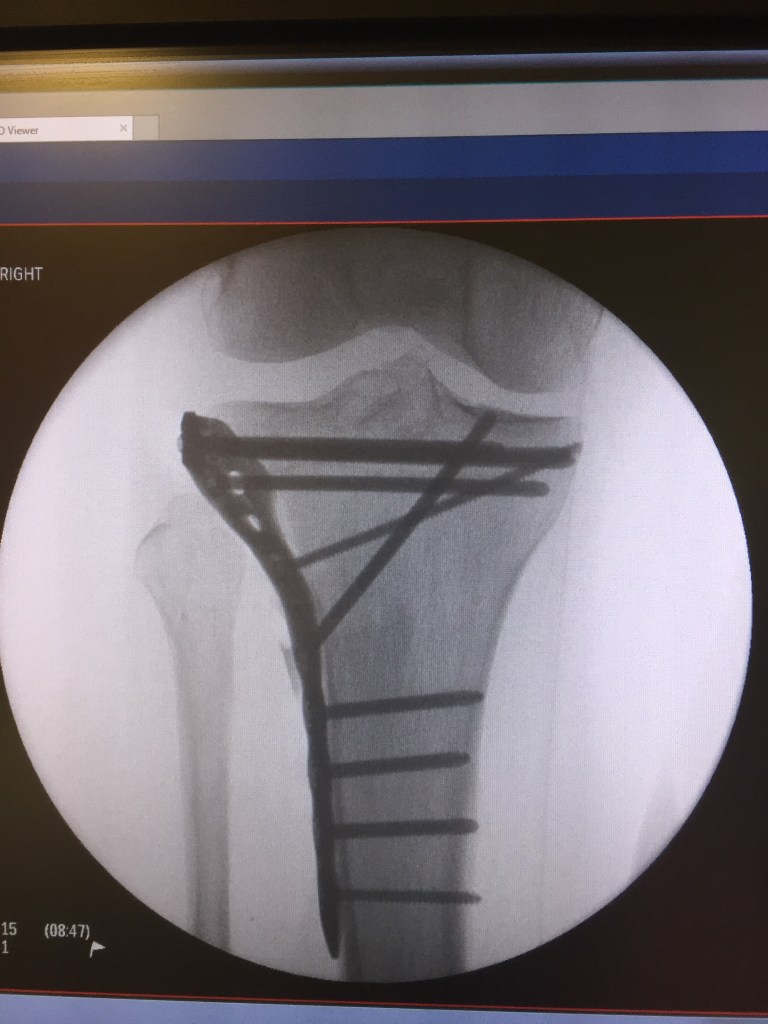

Made return trip to FL – no vehicle issues this time. While taking the Cannon off the trainer and placing the rear wheel back on, discovered a broken spoke on the Hed wheel. Wouldn’t be using the primary randonneuring bike, 2017 Cannondale SuperSix Evo (Cannon), for the weekend rides. Didn’t have any other rim brake wheels in FL. Will have to fix that shosrtcoming depending upon how long it remains the randonneuring bike. Remounted the front light and handlebar bag back on Wili and loaded it in the car. Forgot to take the rear light off the Cannon but thankfully had my secondary light on the back of my helmet. Would only need the lights for a little over an hour as the 300K started at 0600 and the 200K at 0700. Saturday was cold and windy. Rode with Recumbent Man and 2 others for the entire day. Temps were in the high 30s but had a 15+ mph wind which pushed us to a 20.8 mph average for the first 95 miles. The return took about an hour longer and the 3 of us took turns behind Recumbent Man as he pulled us back. Legs definitely lost endurance over the last half of December and first week of January. Sunday was a colder start for the 200K but didn’t feel as cold as the wind was much more mild. Had navigational challenges early on – within first 3 miles, Garmin route indicated a U-turn. Realized the error but had to climb the steep hill twice (rear cassette is only 11-25) and put me at the rear of the group. Ended up catching everyone but Recumbent Man was just departing the turnaround spot as I rolled in. Entire ride for both him and me were solo efforts. Garmin Edge died at the last rest stop with 21 miles to go. Had to use RideWithGPS but for whatever reason, didn’t have any turn-by-navigations so had to have the phone in hand or frequently place/remove it from the handlebar bag. Not a very enjoyable last 20 miles. Front derailleur needs adjustment as the rub in certain gears was very irritating. Successfully completed the ride and enjoyed the post ride pizza! Received bad news 15 minutes before start of 200K – Dad fell and fractured his right hip, shoulder, and 3 ribs along with a collapsed lung.

The only photos are a new pasta casserole (southwestern chicken pasta bake) and the x-ray depicting my father’s new internal hardware.